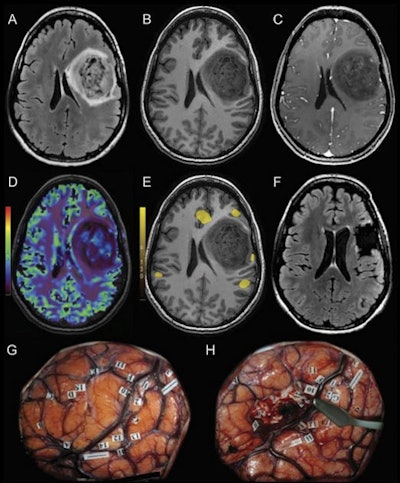

The use of preoperative functional MRI (fMRI) to plan brain tumor resection mitigates negative postsurgical outcomes, according to a study published June 1 in Radiology.

The research results show that fMRI offers a straightforward way to protect the long-term health of brain cancer patients, wrote a team led by Dr. Licia Luna, PhD, of Johns Hopkins Hospital in Baltimore.

To address the knowledge gap, Luna and colleagues investigated overall postoperative morbidity among brain cancer patients, comparing those who underwent preoperative fMRI to those who underwent surgery without fMRI or with the use of standard neuronavigation techniques.

The researchers found that patients were less likely to experience negative outcomes such as neurologic, language, or motor problems after brain surgery when fMRI mapping was performed beforehand (odds ratio, 0.25) and that postsurgical Karnofsky performance status scores were higher in patients who underwent fMRI mapping (this measure ranges from zero to 100, with lower scores indicating a lower chance of a patient surviving serious illness).

The team also found that preoperative fMRI slashed the adverse event rate after brain surgery for tumor resection by almost half compared with surgery without it, at 11% compared with 21%.